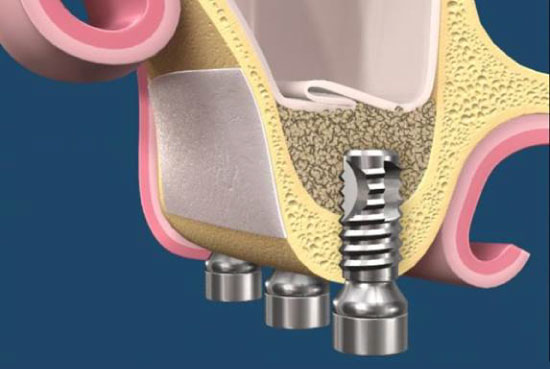

窄植體

近年來,植體的新發展為短植體與窄植體,對於一些特殊位置簡化手術風險迷你植體適用於長期缺牙患者之牙床,或是鄰牙較近、骨脊太窄之病患。可做固定式假牙,也可作活動假牙,更能避免假牙鬆脫之困擾及不適感。

植入迷你植體是一種經濟、實用、快速、簡單的重建方式,特殊之設計及多種尺寸選擇,並利用微創手術植入,傷口小、癒合力快,降低病患的不適感,讓醫師更多了一種選擇,互惠更多不適合傳統植牙的患者,協助提升其咀嚼能力,改善生活品質!(圖47-48)